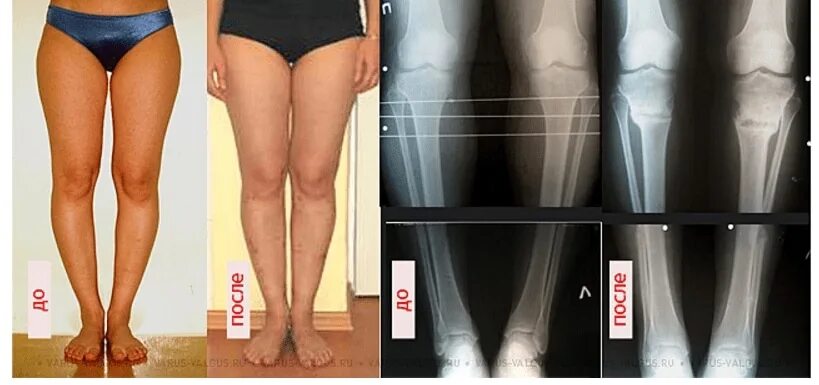

Вальгусная деформация коленных суставов у ребенка